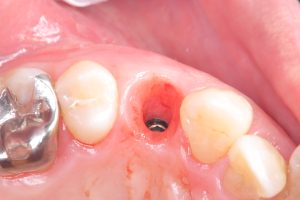

次のお方はオペ後6w、ISQも80台、仮歯まで

次のお方は、本年4月に抜歯即時、ソケットシールド

セミルーナフラップした方の頬側の骨再生画像確認